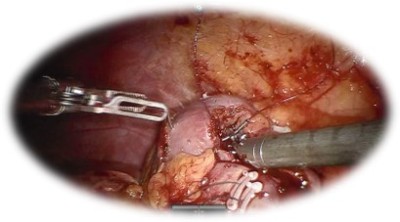

Nefrectomia parțială robotică:

• Presupune îndepărtarea procesului tumoral cu păstrarea parenchimul renal sănătos

• Oferă:

• Sângerare redusă

• Comparativ cu chirurgia laparoscopică, abordul robotic permite scăderea timpului de ischemie.